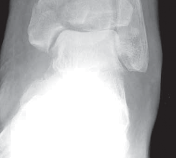

C TECH FIG 1 • A–C. Imaging of 43-C3 plafond injury with anteromedial cortical split allowing best access to injury through anteromedial A B approach.